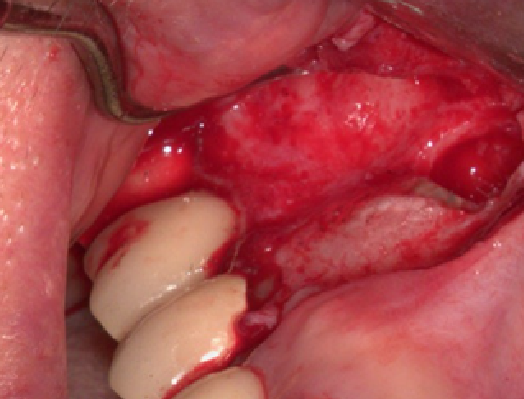

病人因其他院所醫師無法定位根管位置被轉診,在顯微鏡底下可以發現短短不到兩毫米的距離藏有兩根根管(圖中紅線標示處),這是傳統根管治療很難發現的。